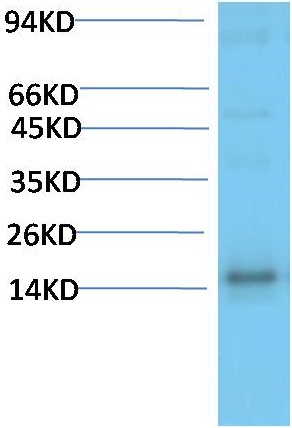

TTR Mouse Monoclonal Antibody(5G9)

Catalog NO.:BE3687

Applications :WB, IHC

| Product Name: | TTR Mouse Monoclonal Antibody(5G9) |

| Recommended dilutions: | WB 1:1,000-2,000 IHC 1:100-200 |

| Specificity: | The TTR Mouse Monoclonal Antibody can detects endogenous TTR proteins. |